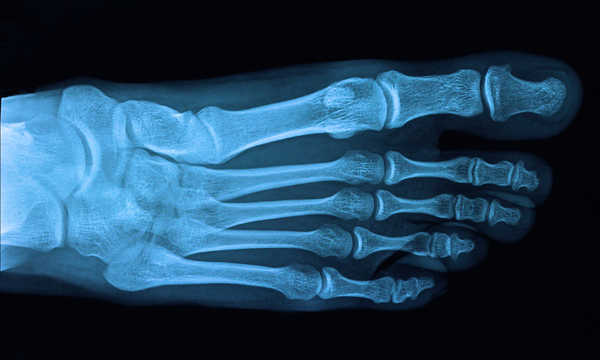

• szczegółowa diagnostyka obrazowa (RTG w obciążeniu)